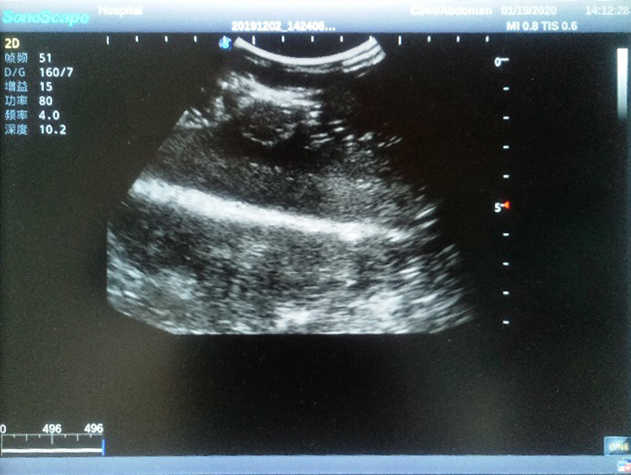

Product size(mm) 308×228×150

2)  Each model contains 8 space-occupying lesions of varying sizes, different in touch, elasticity and ultrasonogram

4) Biomimetic material allowing users to see clear and real normal tissues and space-occupying lesions that are hyperechoic, hypoechoic and isoechoic as they would see in the clinical environment